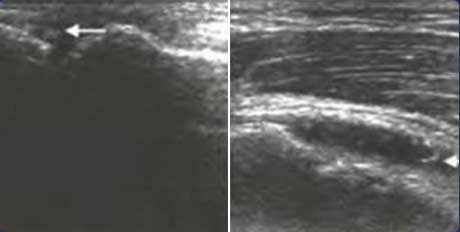

四、早期发现软组织改变、评定骨质侵蚀受损层级

在痛风初始阶段,肌骨超声就可清晰的发现患病关节周围软组织团状稍高或强回声、不规则形变薄、内部血流增多以及邻近骨皮质回声毛糙不平滑、连续性中断或缺损情况,判断软组织受损程度。对于慢性痛风的超声检查,在痛风石旁可发现骨皮质不连续、骨表面常呈虫蚀样缺损或骨赘形成,从而评定痛风病程长短及对骨质造成的不同层级的损害。

骨质侵蚀

跖趾关节骨质表面的不连续即为骨质侵蚀

软组织受损

肿胀关节内部回声不均匀,痛风结节周围软组织边缘欠规则。